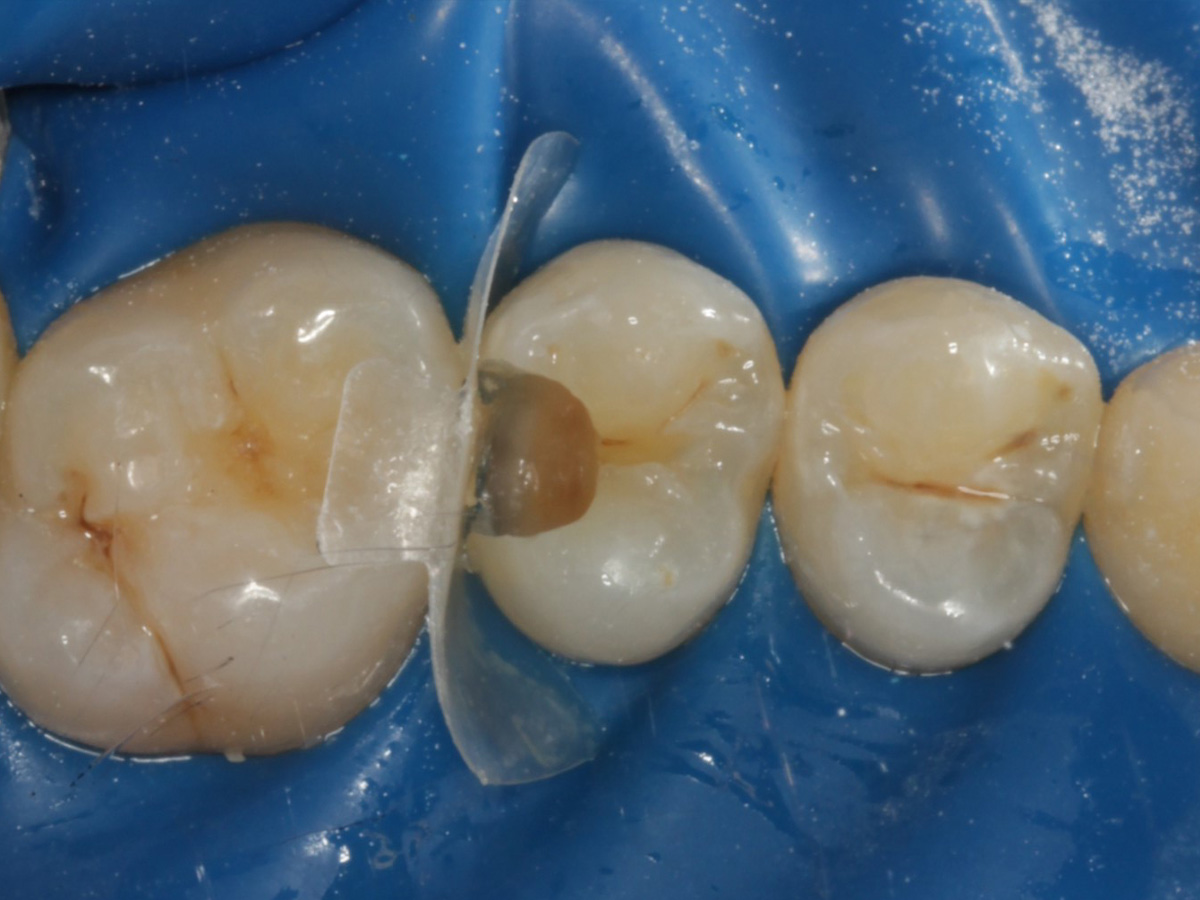

Abbildung 4

Schutz des Nachbarzahnes und des Kofferdams mit wiederverwandter Bioclear Biofit Matrize (gereinigt und sterilisiert); Separation zur Applikation der Matrize mit Heidemannspatel